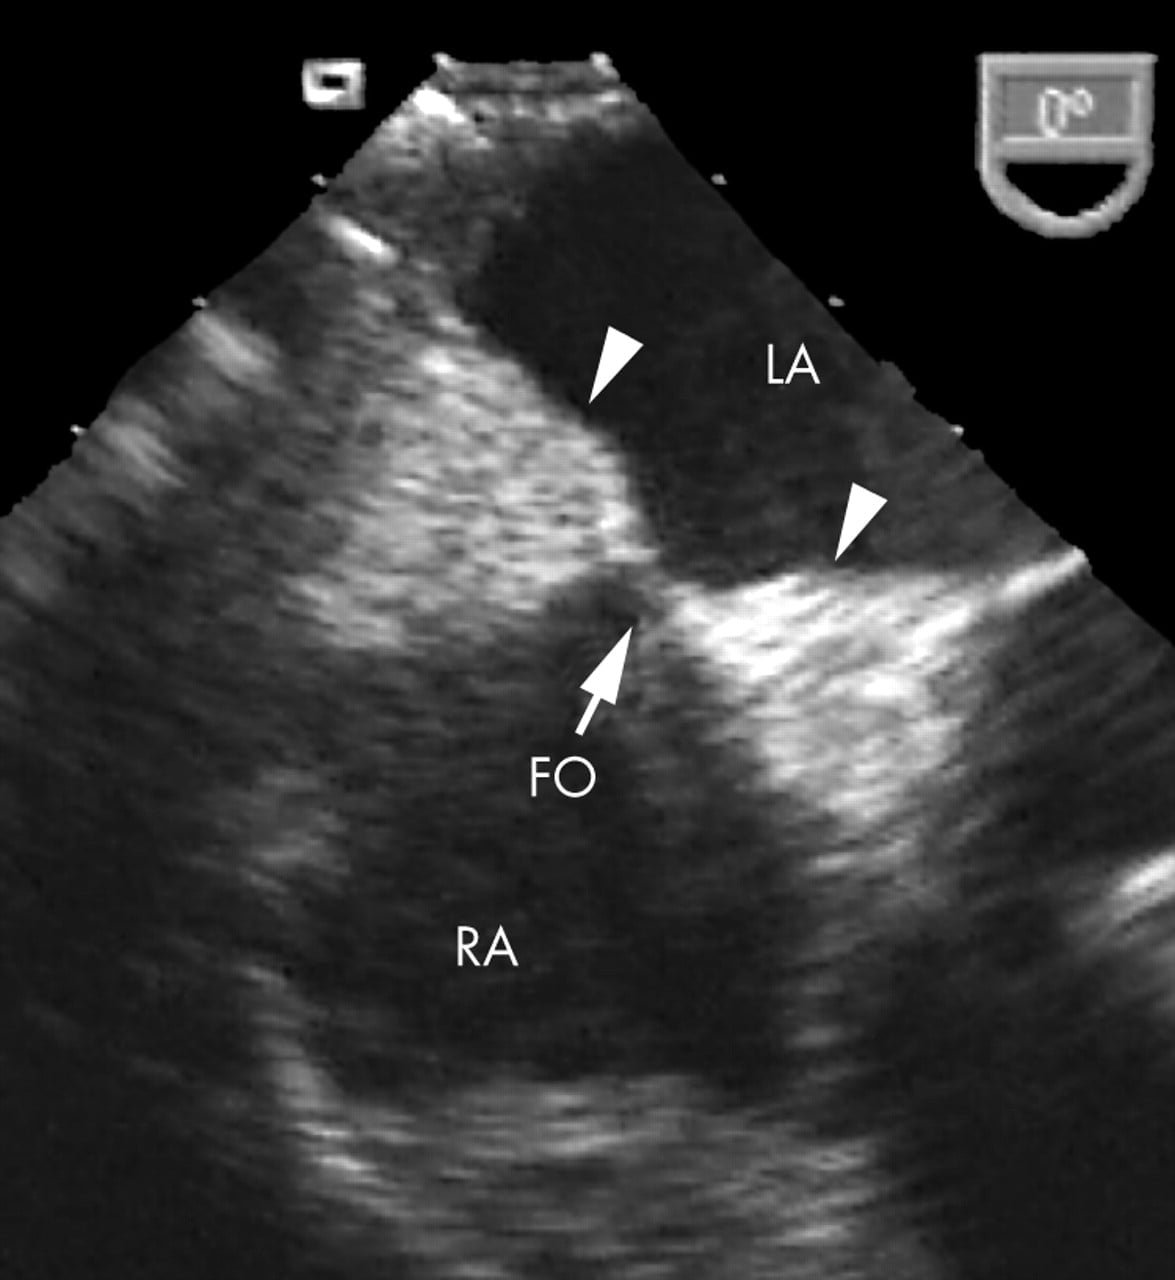

A hipertrofia lipomatosa do septo interatrial é uma condição benigna caracterizada pelo acúmulo maciço de gordura no septo interatrial que ultrapassa 2 cm de espessura. Por  poupar a região da fossa oval, acometendo as regiões dos istmos, é também denominada de septo interatrial em formato de haltere ou ampulheta. (Ver também: Forame Oval Patente (FOP) – Definição, diagnóstico e tratamento)

Hipertrofia Lipomatosa do Septo Interatrial

Hipertrofia llipomatosa do septo interatrial

(LA: átrio esquerdo; RA: átrio direito; FO: fossa oval)